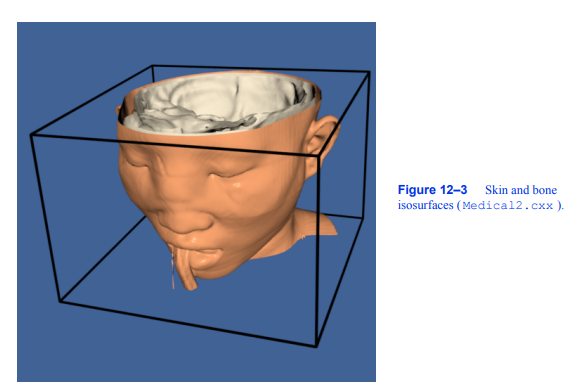

我们可以通过多种方式改进这种可视化。首先,我们可以为皮肤选择更合适的颜色(和其他表面属性)。我们使用vtkProperty方法SetDiffuseColor()将皮肤颜色设置为肉色。我们还在皮肤表面添加了一个镜面组件。接下来,我们可以添加与各种解剖特征相对应的额外等值面。这里我们选择通过添加额外的管道段来提取骨表面。它由筛选器vtkMarchingCubes、vtkPolyDataMapper和vtkActor组成,就像我们对皮肤所做的一样。最后,为了提高系统的渲染性能,我们从输出中创建三角形条

轮廓的过程。这需要添加vtkStripper。图12 - 3显示了生成的图像,下面是该管道的c++代码。